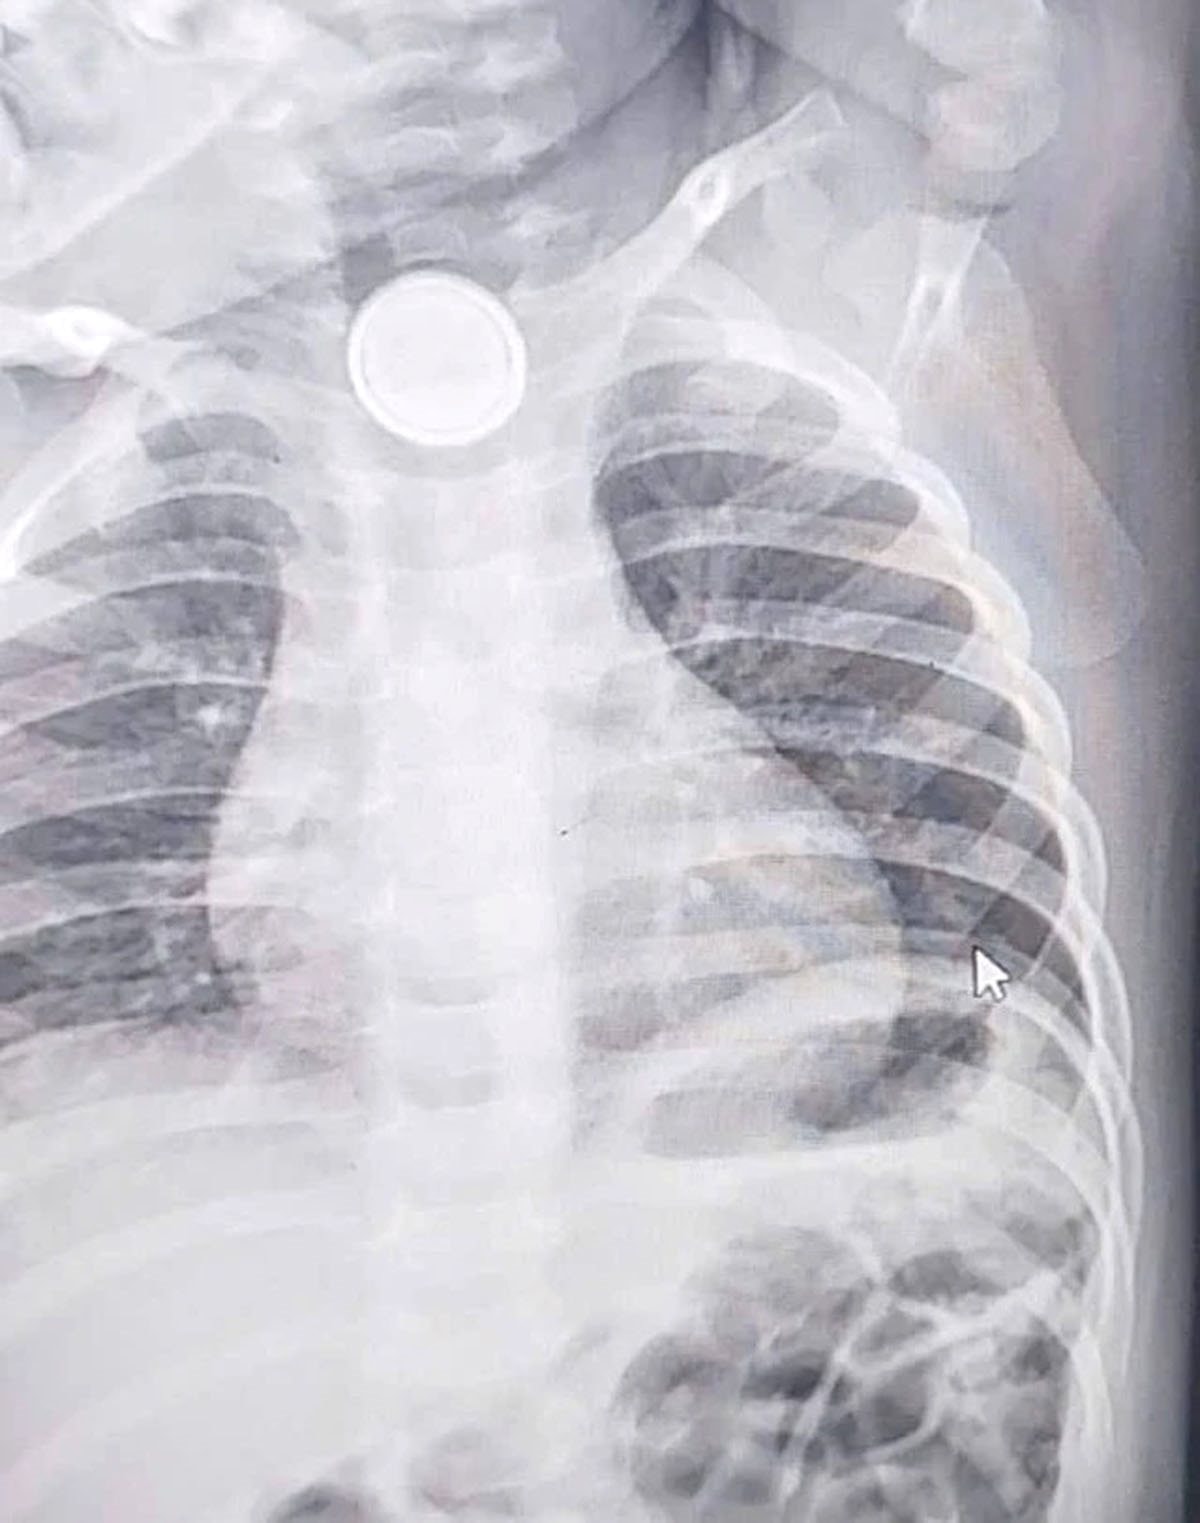

Qua thăm khám lâm sàng kết hợp chụp chiếu, các bác sĩ xác định pin cúc áo đang mắc kẹt tại thực quản.

Đáng chú ý, thời điểm nhập viện đã muộn, khi dị vật lưu lại trong cơ thể khoảng 4 ngày. Quá trình này đã gây tổn thương nghiêm trọng, làm niêm mạc thực quản bị bỏng sâu, viêm loét rõ rệt.